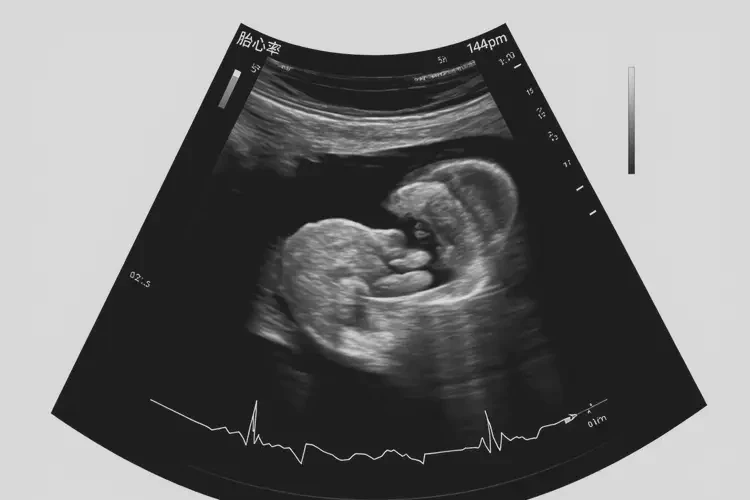

胎心率144次/分钟在怀孕3周时是正常的。

在怀孕早期,胎心率通常在120-160次/分钟之间波动。胎心率是指胎儿心脏每分钟跳动的次数,它反映了胎儿的健康状况。在怀孕3周时,胎儿的心脏已经开始跳动,但由于胎儿还很小,胎心率可能会有一定的波动。

胎心率的正常范围:在怀孕早期,胎心率通常在120-160次/分钟之间。这个范围是根据大量的临床数据和研究得出的,被认为是胎儿健康的正常指标。

胎心率144次/分钟在怀孕3周时是正常的。孕妇应该定期进行产前检查,及时了解胎儿的健康状况。如果发现胎心率异常,应该及时就医,以便得到及时的治疗和处理。